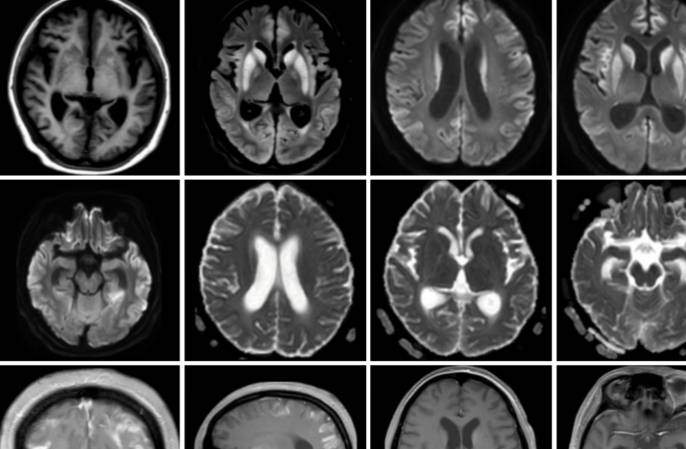

14岁,男,烦渴多尿多饮2月,否认糖尿病史。辅查:低渗性多尿,性激素中仅泌乳素升高,肝损害,双肾积水。

26岁,女,右侧肢体无力伴意识模糊1月余。既往史:月经周期不规则,两年前停经。1年前体重增加18公斤,伴双手、脚踝对称性肿胀,面部浮肿。3月前出现多尿、多饮,空腹血糖升高,每天尿液超过10升。既往无烟酒、毒品接触史。查体:体重指数34.6,皮肤、口腔粘膜、甲床苍白。皮肤干冷,双侧手、脚踝水肿,阴毛稀疏。神经查体:昏睡,表达性失语症。右侧周围性面瘫,右上肢完全瘫痪,右下肢部分瘫痪。左侧肌力正常。右侧腱反射消失,左侧腱反射正常。右侧病理征阳性,左侧病理征阴性。无感觉异常。辅查:贫血,高钠血症伴低渗性多尿。血糖高,甲减,性激素示FSH、LH、PRL降低。ESR、CRP升高,狼疮、干燥等风湿抗体阴性。

答案:朗格汉斯细胞组织细胞增生症。朗格汉斯细胞组织细胞增生症是一组少见的瘤样病变,发生在骨组织的反应性、非肿瘤性、增生性疾病。多见于20岁以下青少年。其临床表现:骨骼病损、皮肤黏膜损害、淋巴结损害、肝脏及脾脏损害、肺脏损害、女性生殖系统损害、内分泌系统损害、其他表现(长期发热、胃肠道受累、中枢神经系统受累等)。影像:1)中枢神经系统:矢状位可发现垂体后叶T1WI高信号消失。部分病人可见垂体柄增粗或下丘脑孤立性强化结节。2)呼吸系统:胸部CT:双肺多发结节并弥漫分布大小不一囊性病变,中上肺野为著,囊壁厚薄不规则。4、活检:1)光镜:朗格汉斯细胞灶状或片状排列是本病的特征;2)电镜:朗格汉斯细胞中特有的Birbeck颗粒;3)免疫组化:S2100蛋白阳性、CD1a(冷冻切片)或MAb010(石蜡切片)阳性为其特征。